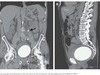

▲女子腹痛多年,檢查才發現自己體內竟然藏了一根針。(圖/翻攝自大陸網站)

中國醫科大學遼陽中心醫院普通外科副主任醫師任慶華表示,檢查發現,這根針是從胃後壁穿出來,連著胰腺又靠近脾動脈,取針若一個不小心就會造成大失血,幸好手術於8月順利完成,王小姐目前已順利出院。